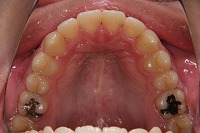

上顎

反対咬合と下顎が出ている事を主訴に来院された、初診時18歳1か月の男性です。診断「上顎骨の後方位による骨格性反対咬合」非抜歯での矯正治療と、下顎を後退させる外科手術を併用して治療を行いました。